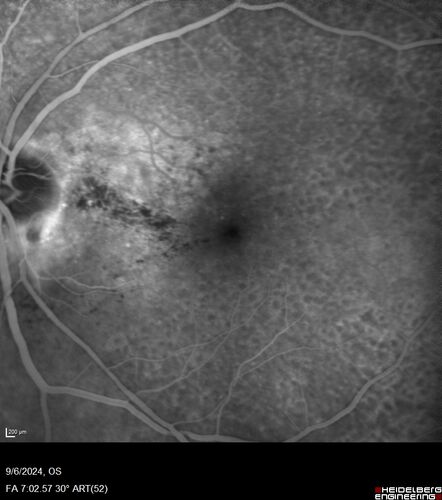

Peripapillary CNVM No Treatment

85 year old with peripapillary CNVM watched for many years.